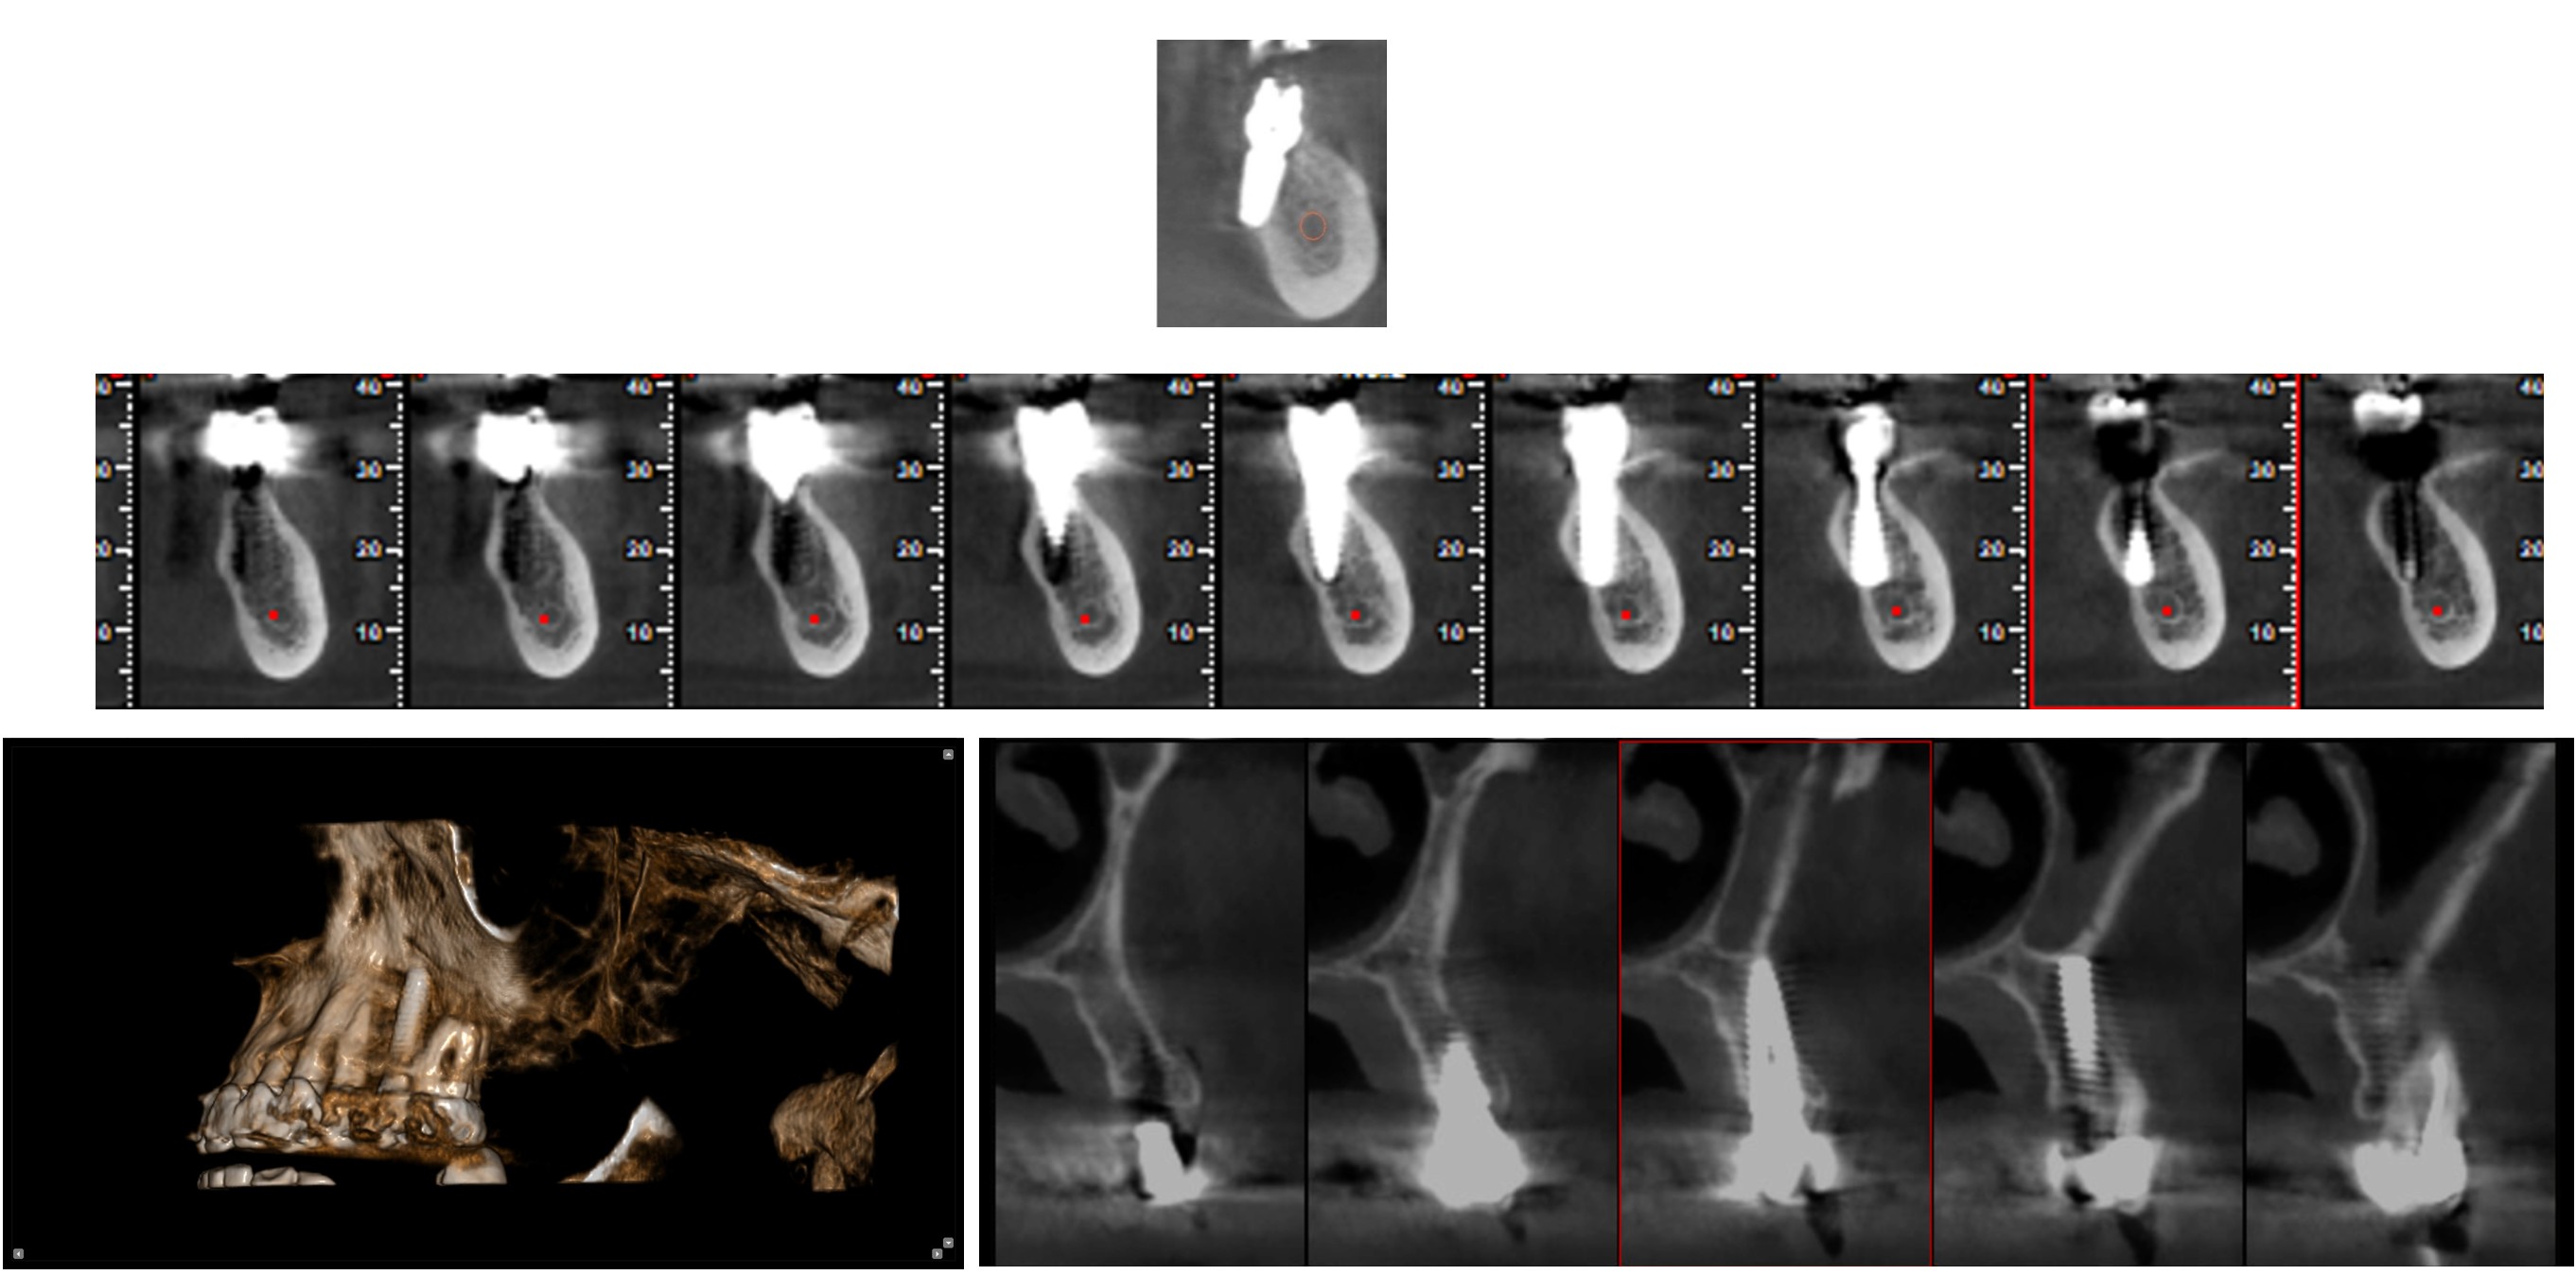

Aποτελεί μια απεικονιστική μέθοδο εκλογής για τη γναθοπροσωπική χώρα όταν απαιτούνται πληροφορίες για τη τρίτη διάσταση και απεικόνιση 1:1. Η απεικόνιση της τρίτης διάστασης συμπληρώνει τις πληροφορίες των απεικονιστικών προβολών δύο διαστάσεων όπως οπισθοφατνιακών, πανοραμικών και κεφαλομετρικών ακτινογραφημάτων, ξεπερνώντας τους περιορισμούς αυτών των εξετάσεων, κυρίως την αλληλεπίθεση των δομών και την παραμόρφωση της εικόνας.

Η απεικονιστική μέθοδος ΥΠΟΛΟΓΙΣΤΙΚΗΣ ΟΓΚΟΜΕΤΡΙΚΗΣ ΤΟΜΟΓΡΑΦΙΑΣ ΚΩΝΙΚΗΣ ΔΕΣΜΗΣ χρησιμοποιείται ευρέως σε όλα τα πεδία της οδοντιατρικής. Η διερεύνηση της ανατομίας, ο σχεδιασμός τοποθέτησης εμφυτευμάτων, ο προεγχειρητικός έλεγχος, η διερεύνηση παθολογίας, η ενδοδοντία, η περιοδοντολογία, η εξέταση της κροταφογναθικής διάρθρωσης, είναι ενδεικτικά μερικά από τα πεδία εφαρμογής της.